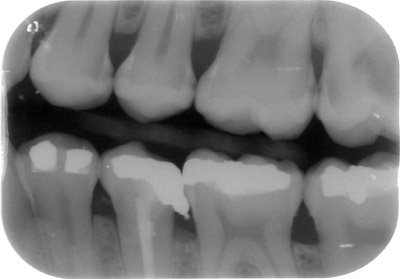

• la realització de dos radiografies intraorals (aletes de mossegada) o extraoral (ortopantomografia ) per arribar al diagnóstic més acurat.

A més, és molt important la realització de radiografies de dignòstic, tant a la primera visita com a les futures revisions, ja que el major nombre de les càries comencen als punts de contacte entre les dents o queixals, i aquests són innaccesibles visualment amb una exploració convencional.

aletadreta aletaesq   ortopanto